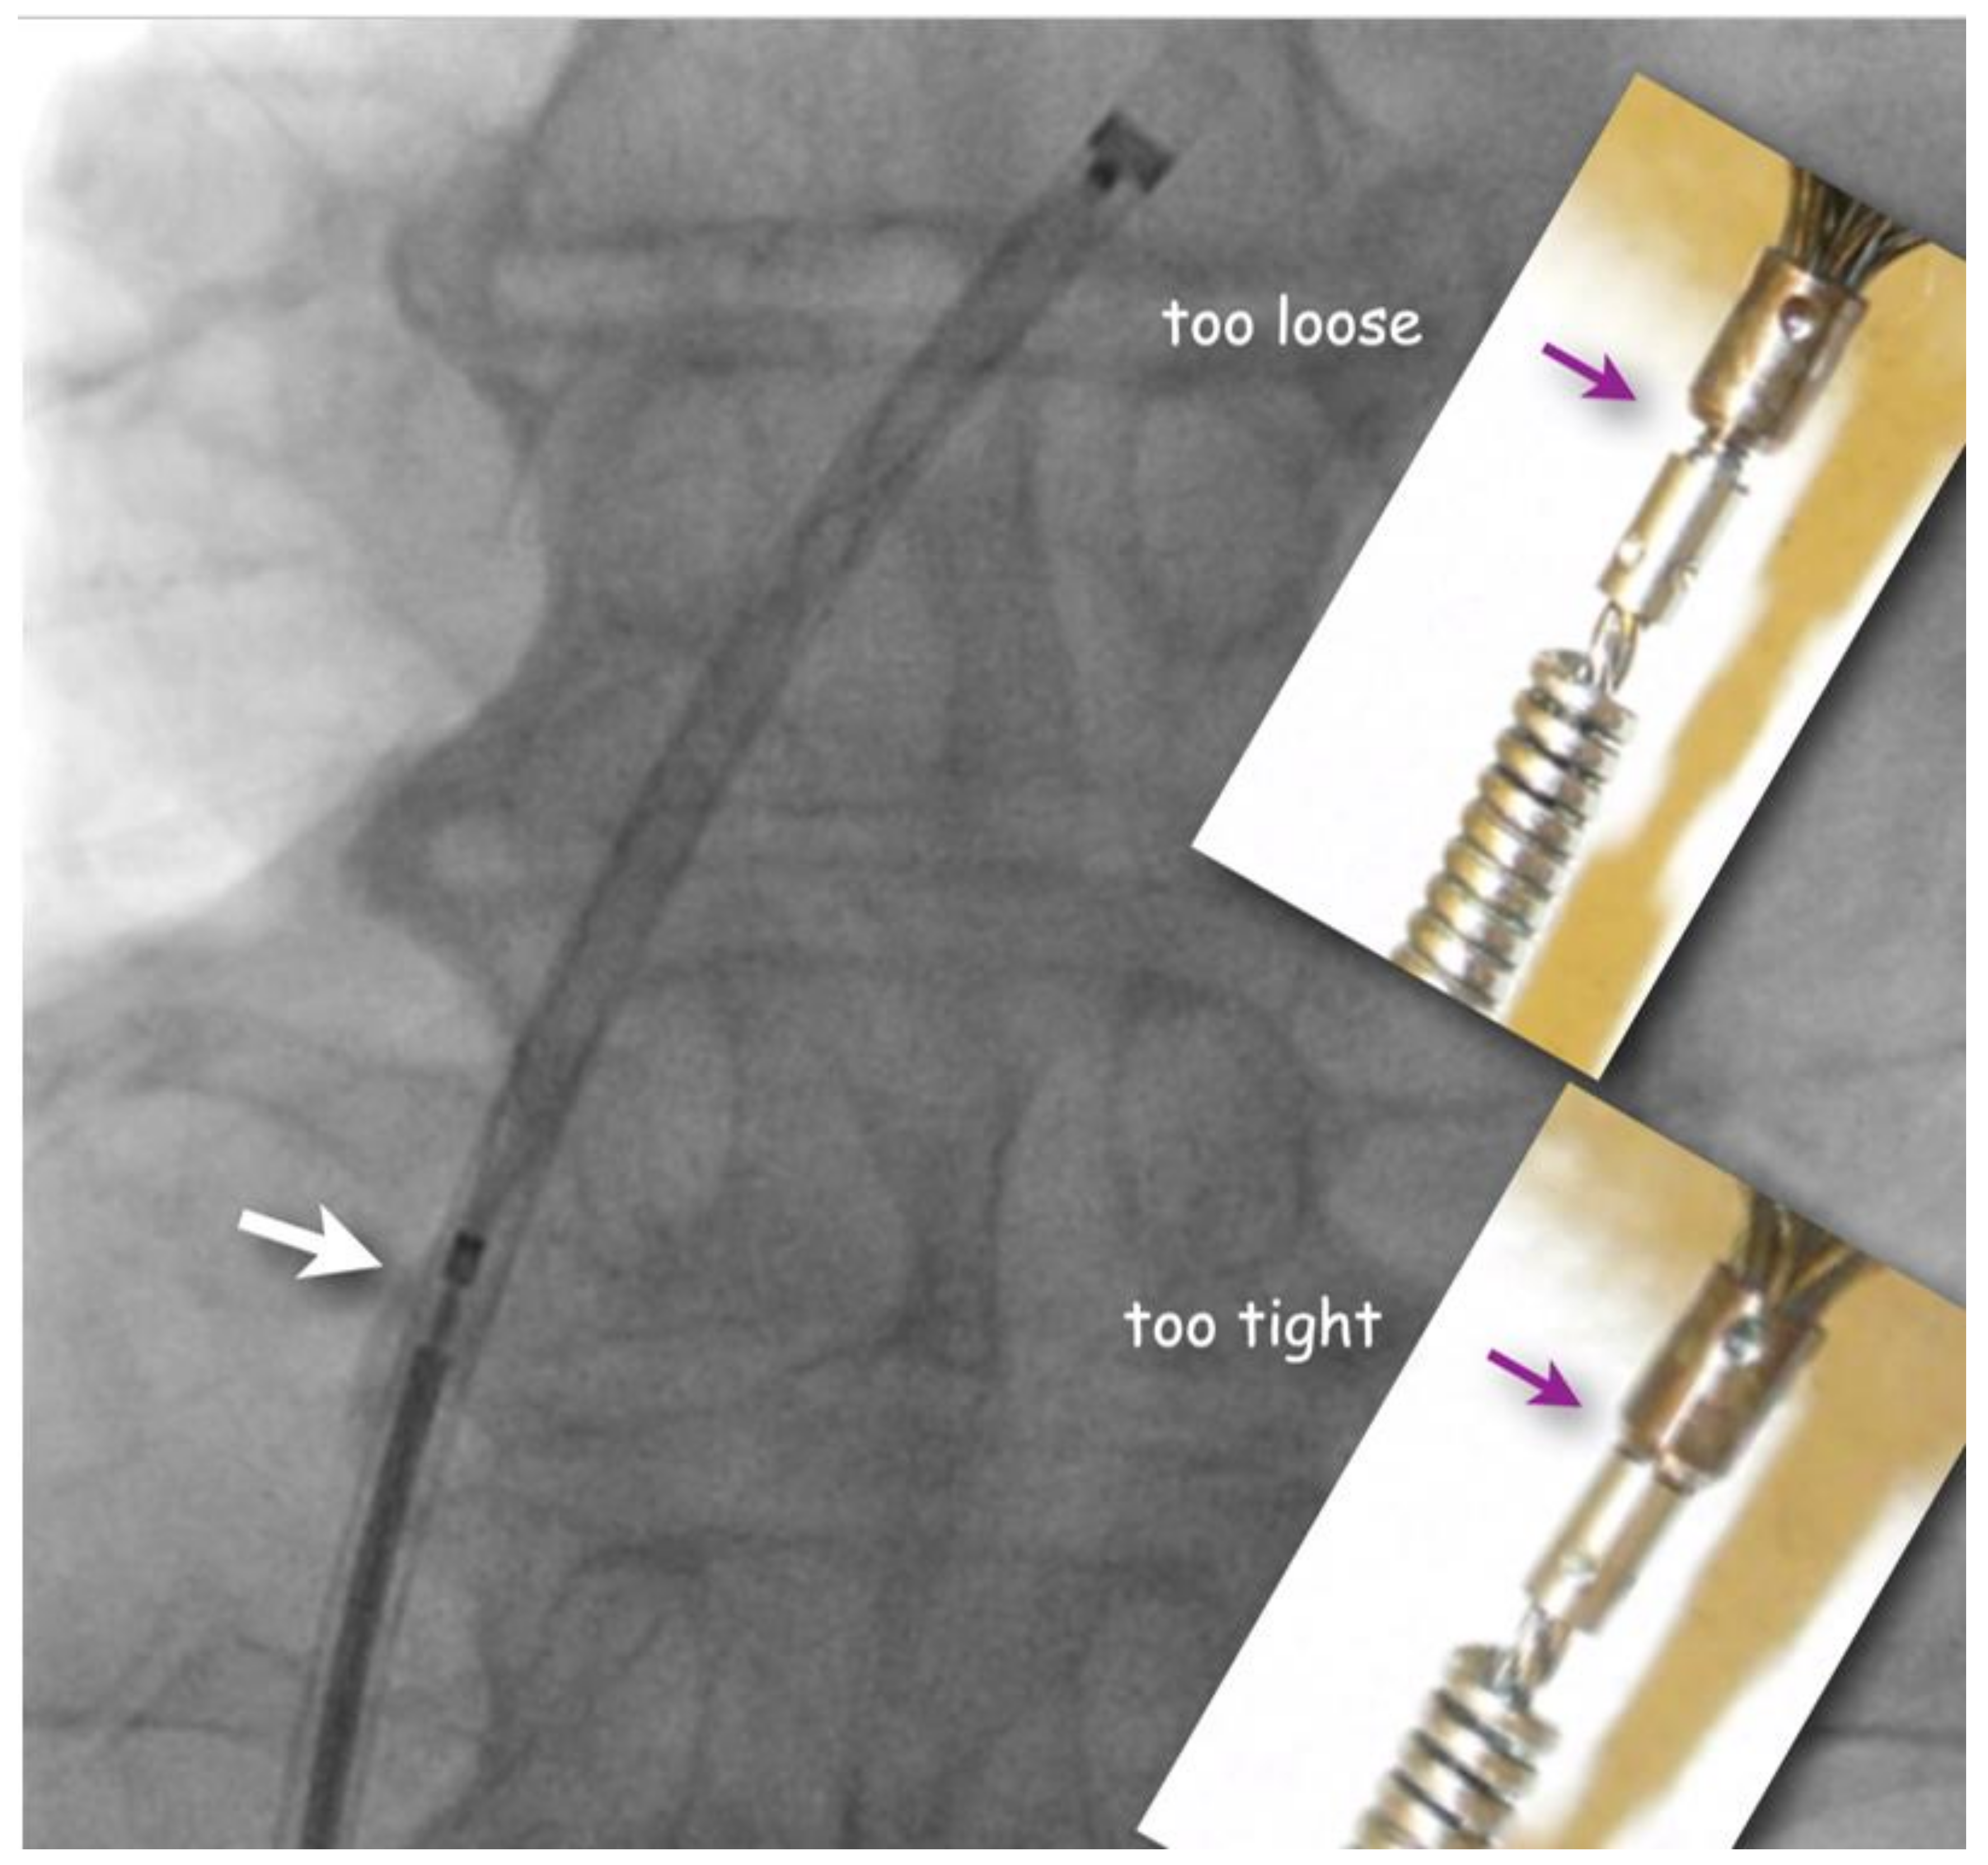

The flushed short loader sheath containing the selected preloaded occluder with its tip just peeking out is connected to the backbleeding sheath and the device is advanced to the distal tip of the sheath without any simultaneous flushing. Before exiting the sheath, it is made sure that the screw used for fixing the original Amplatzer device and most of its derivatives during delivery be still properly tightened, but not too much. A small gap ought to be visible (Figure 2). If there is no gap, one or two full left (counterclockwise) turns are recommended during which usually an unblocking click is felt. This assures that the screw is not tightened overly fast so that the occluder would swivel with the loader cable rather than being released when the unscrewing is attempted at the end of occluder positioning. Too generous a gap documents inadvertent partial unscrewing of the occluder on the way up through the sheath. That needs to be corrected with turning right (clockwise) on the loading cable. In the extremely rare case that the screw is seen to be completely disconnected, the device is not implanted but pulled out of the sheath with a snare and reattached properly before reinsertion and implantation.

A small gap (white arrow) between pusher screw-collar and screw-nut on the device guarantees that the occluder is still safely attached but will be easily detachable once positioned. The inserts show screw positions that should be corrected either with turning the pusher cable clockwise (if too loose) or counterclockwise (if too tight) before advancing the occluder out of the sheath.

Figure 2. Fluoroscopic check of correct attachment of Amplatzer(-like) occluders (frontal view).